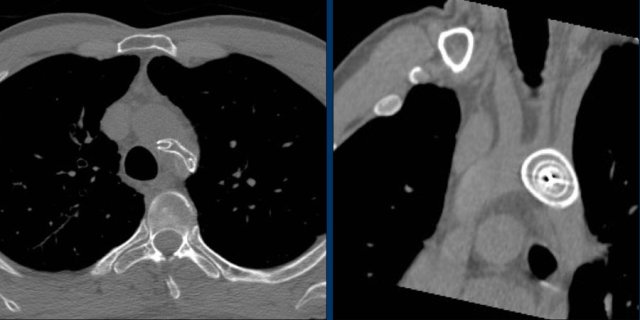

Transverse CT-image and coronal reconstruction of the same patient.

This patient has three closure devices.

Dislocation of the closure device.

CT demonstrates, that the Amplatz device is dislocated into the aortic arch.